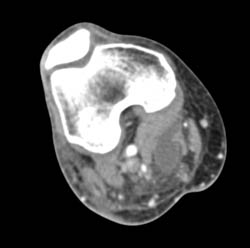

Repair of Nonunion of Clavicle